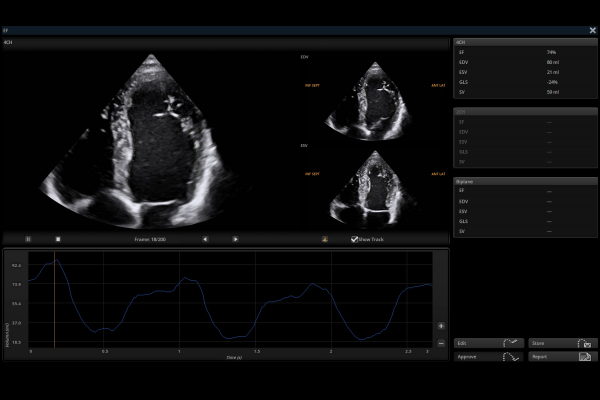

Intelligent Breast Solutions on the Workstation

Automatic lesion detection powered by AI identifies suspected area and traces the lesion from multiple sections. Quantitative coordinate position and graphic indication will be displayed for precise lesion localization.

Lesion stereo images are generated from volume data rendering. It provides intuitive and detailed information for better observation and lesion localization.